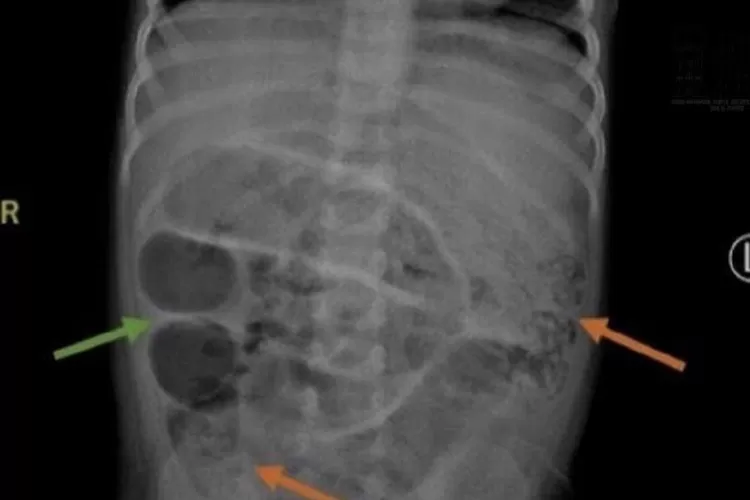

Hasil Rontgen Anak yang di Perutnya Terdapat Cacing Pita. (instagram.com/jemberinfo_)